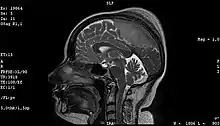

Imaging

Medical imaging plays a central role in the diagnosis of brain tumors. Early imaging methods – invasive and sometimes dangerous – such as pneumoencephalography and cerebral angiography have been abandoned in favor of non-invasive, high-resolution techniques, especially magnetic resonance imaging (MRI) and computed tomography (CT) scans,[38] though MRI is typically the reference standard used.[41] Neoplasms will often show as differently colored masses (also referred to as processes) in CT or MRI results.

More recently, advancements have been made to increase the utility of MRI in providing physiological data that can help to inform diagnosis and prognosis. MRI itself is sufficient in identifying the brain tumor’s location and morphology, but other types of MRI may be used on top of that, such as MRA, MRS, pMRI, fMRI, and DWI. These imaging techniques help doctors and surgeons to diagnose the type of tumor, to plan for surgery, and to assess treatment and radiation/chemotherapy.